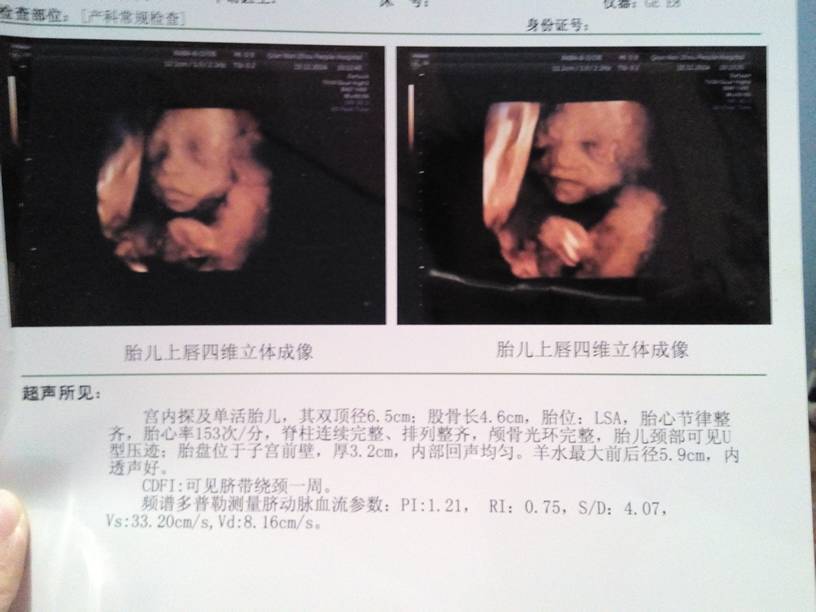

今天刚做的四维彩超,医生说一切正常,终于放心了 大家给看看是男孩女孩… 今天刚做的四维彩超,医生说一切正常,终于放心了。大家给看看是男孩女孩…… 点击展开 套路不要太深哦 2014-11-13 21:35 为您推荐: 其他回答 祝宝妈好孕 159*****442_WHKY 2014-11-13 21:52 女孩吧。管他男孩女孩都是我们的心头肉,十月怀胎啊 这该死的爱 2014-11-13 21:52 看不出来。。 ℡爱过知情深╮ 2014-11-13 21:45 恭喜,好像是男宝 杨静 2014-11-13 21:44 看不出来! - 哈尼, 2014-11-13 21:39 加载更多 相关问题 四维彩超医生能不能看出男孩女孩? 今天做了三维彩超大家帮忙看看,能看出男孩女孩吗?BPD:63 HC; 236 AC;200 今天去做的四维彩超,孕22周+1周,看看怎样,左心室见大小为2x2mm强光点是什么回事,问医生不给